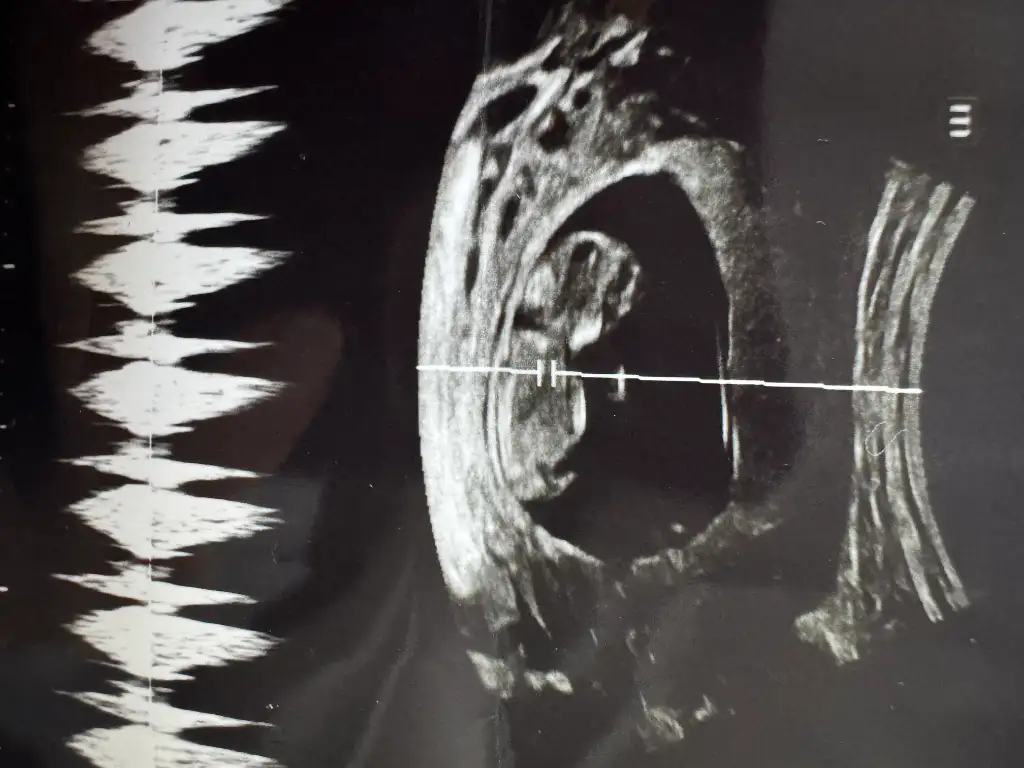

Seninkini atar mısın canım bende bakayım.Ay benimkine benzettim nub kısmını![]()

Benim için farketmez ama eşim kız diye ölüyor.Evet nubu duz gibi geldi bana canim

Belli olunca yazacağım canım. 2 hafta sonra bir daha göreceğiz belki o zaman söyler.Nub yukarı doğru sanki erkek gibi![]()